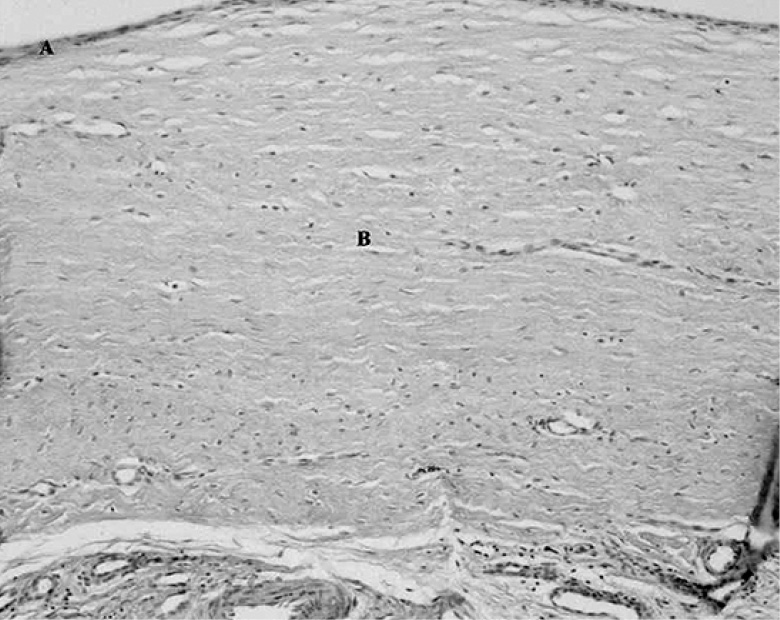

При гистоморфологическом исследовании было выявлено, что стенка кисты Бейкера устроена аналогично икроножно-полуперепончатой бурсе, при этом имелись признаки склероза, а в ряде случаев – слабовыраженная лимфоцитарная инфильтрация (рис. 1, 2). В строении стенки кисты чётко выделялись 2 слоя:

- внутренний – синовиальный (представленный синовиальными клетками),

- наружный – фиброзный слой (представленный плотной неоформленной соединительной тканью).

Рис. 1. Срез стенки кисты Бейкера (Г–Э, ×100). А – атрофичный синовиальный слой. B – фиброзный слой.

Fig. 1. A section of the wall of the Baker cyst (G-E, ×100). A – atrophic synovial layer. B – fibrous layer.

Клеточный состав стенки кисты был представлен фиброцитами, макрофагами, однокапельными адипоцитами и лимфоцитами. В обоих слоях выявлены единичные кровеносные сосуды (в основном капилляры). Электронограммы демонстрировали исчерченные коллагеновые волокна в обоих слоях стенки кисты. Клетки фиброцитов/фибробластов располагались между многочисленными жировыми клетками, имели слаборазвитые органеллы, многочисленные отростки (рис. 3).